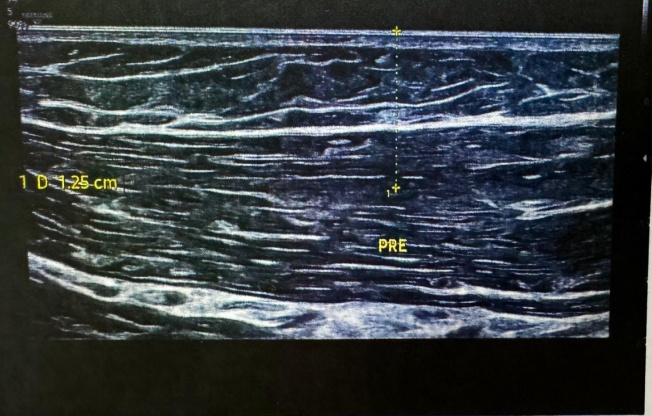

Fig. 1 Fig. 2

Fig. 3 Fig. 4

Fig. 1-6: Ultrasound image report

Ultrasonography of right elbow joint

No significant free fluid seen in elbow joint region.

The visualized cortex of distal humerus and proximal radius appears normal and show no breach at present scan.

Visualized muscles and tendons appear normal and show no tear at present scan.

No evidence of any inflammatory changes seen in elbow joint region. There is a tiny well defined hypoechoic area approx 1.25 cms from the skin seen in proximal ECRB (extensor carpi radialis brevis).